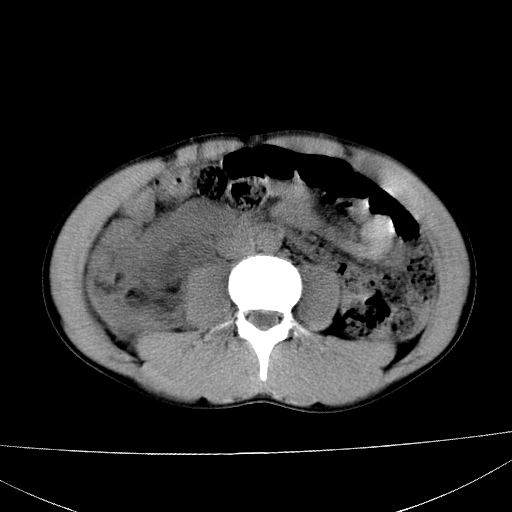

标题: CT15860:男,21岁,腹部外伤2小时伴胸疼。 [打印本页]

标题: CT15860:男,21岁,腹部外伤2小时伴胸疼。

肝肾挫裂伤,右肾周及包膜下血肿,腹腔积液,不排除空腔脏器穿孔,建议行增强检查

肝、右肾包膜下血肿,右侧腰大肌及腹膜后血肿;腹腔少量积血;腹腔疑有少量游离气体伴肠破裂。

1肝挫伤伴腹腔积液。2右肾挫裂伤伴右肾包膜及肾后间隙肿血肿。3右肾脏周围的积气,十二指肠显示结构不清,考虑十二指肠降部破裂可能性大。